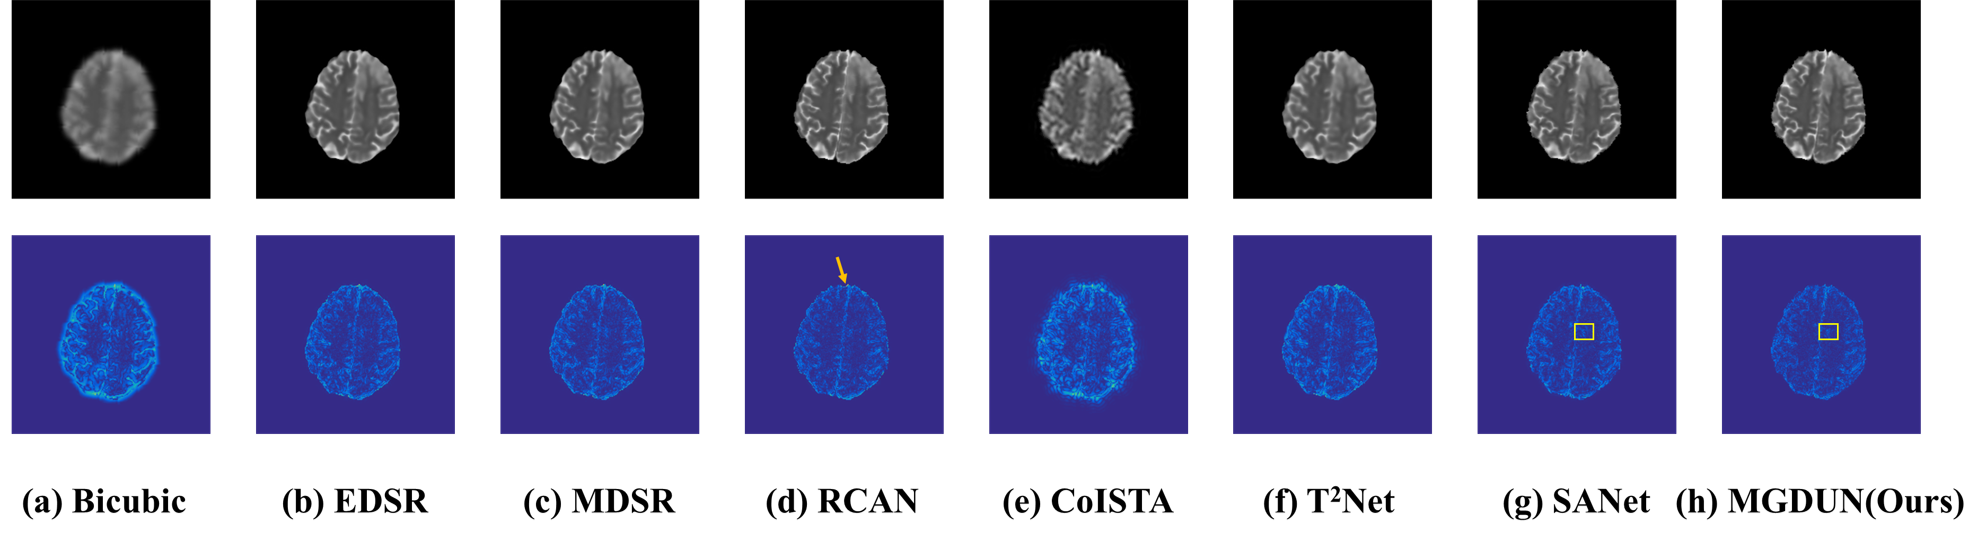

Refer to caption

Figure 4. Qualitative comparison of all methods on BraTs dataset. The first row visualizes the visual effects of different methods, and the last row visualizes the error map between the SR results and the ground truths.

4.3.2. Qualitative results

We provide qualitative comparison results on the IXI dataset as well as the BraTs dataset and their corresponding error maps in Fig. 3 and Fig. 4. The texture of error maps represents the restoration error, the smoother the texture, the better the reconstruction. As we can see, the input has significant aliasing artifacts and lacks anatomical details. It can be noted that our model recovers the image with fewer visible artifacts and reconstructs more details than other competing methods. The quality improvement achieved by MDCUN may be associated with the full usage of the feature maps from the former stages to refine the final results.